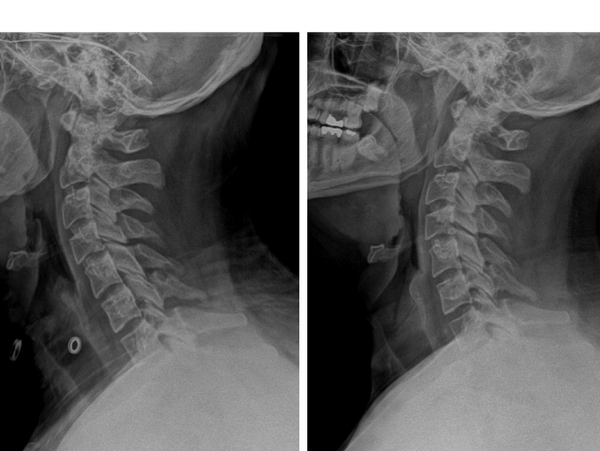

One of our model patients recently completed a full corrective chiropractic care plan with outstanding results. At the start of care, his forward head posture measured 61 mm—a significant deviation that placed extra stress on his neck and spine. Through consistent adjustments, customized exercises, and adherence to his care plan, his posture improved dramatically. By the end of his program, follow-up X-rays showed his forward head posture had reduced to just 14 mm. This measurable change not only improved his posture and appearance but also reduced tension, discomfort, and risk of long-term spinal degeneration. His success is a powerful example of what’s possible with dedication and the right corrective care approach.